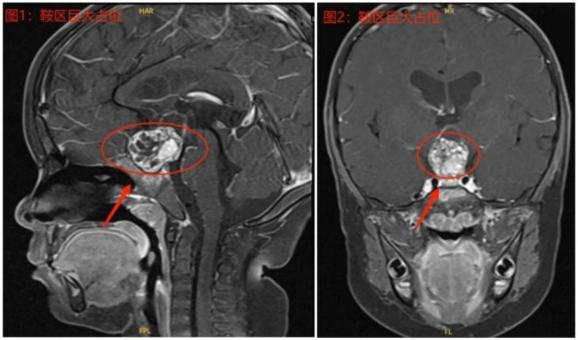

进一步经过头颅影像学检查后,他们终于找到了导致小羽不长高的另一个“凶手”——脑部鞍区有一个巨大占位。

◎ 检查显示,小羽的鞍区有一个巨大占位。/医院供图02

为了明确小羽这个颅内占位的性质,制定下一步治疗计划,梁立阳召集了包括儿科神经内分泌专科、儿科肿瘤专科、放射科、肿瘤放疗专科、神经外科、分子诊断中心及护理团队在内的多学科会诊团队,对小羽的病例资料进行讨论,初步考虑占位的性质为颅咽管瘤,需要手术切除治疗。对此,多学科会诊团队制定了术前、术中、术后的激素替代治疗、液体维持、电解质监测、手术切除方式等详细方案。

颅咽管瘤是生长于脑部鞍区的一种上皮原性良性肿瘤,发病率为0.5-2/100万人。虽然颅咽管瘤是良性肿瘤,但它的生长方式却与恶性肿瘤相似,增大的肿瘤会挤压或压迫垂体、垂体柄等部位,破坏正常垂体结构,引起垂体内分泌功能障碍。

此外,巨大的肿瘤还会压迫视交叉、引起脑积水等。手术切除是治疗颅咽管瘤的首选方法。